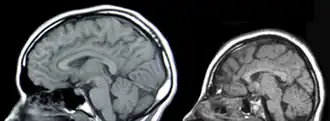

| Tomografia da cabeça. Esquerda: normal. Direita: microcefalia. | |